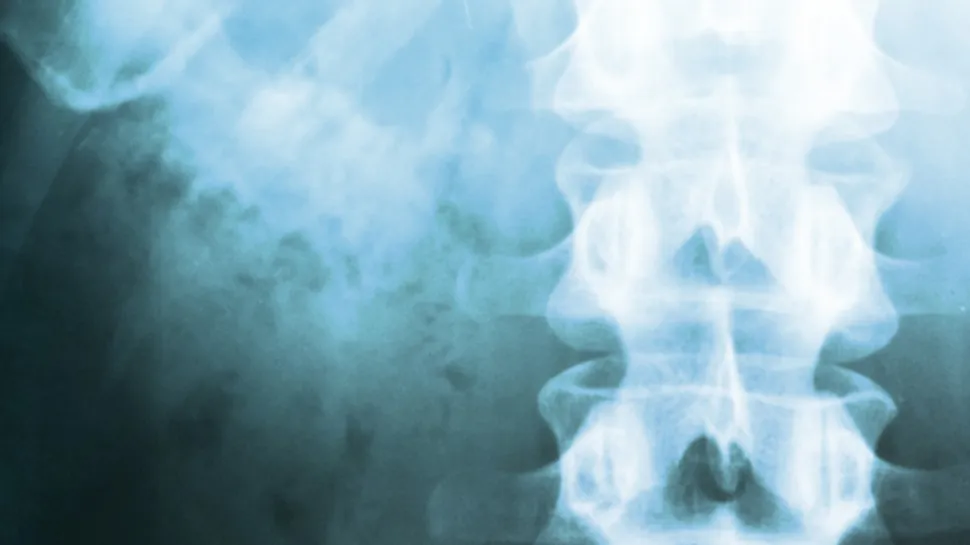

Can Myeloma Bone Damage Be Repaired?

Out of curiosity, have any of you been able to see a difference pre and post treatment on your PET, MRI or X-ray scans? We'd love to hear about your experiences in the comments below.